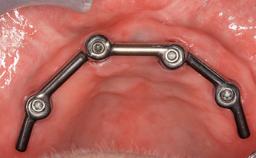

Fixed and removable prosthodontic implant therapy for restoration of the edentulous maxilla is both complex and challenging. Careful assessment and planning is needed in each individual case to explore whether a fixed or a removable solution will be the more suitable to satisfy the patient’s preference for optimal esthetics, phonetics, comfort and function. This Learning Pathway explores the prosthodontically driven treatment planning based on structured assessment, considered diagnosis and practical application in clinical case examples.